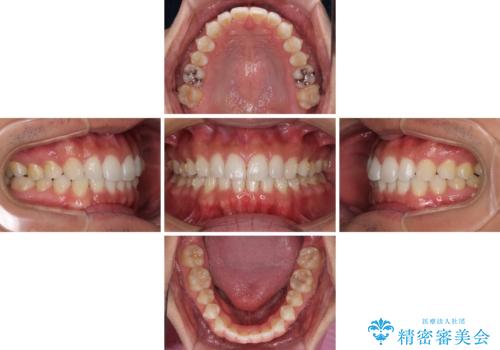

- 上下前歯のデコボコを気にして来院された患者様です。

以前矯正をした後戻りということで、歯列不正はそれほど大きくなかったため、インビザライン・ライトを用いて矯正治療を行うこととしました。

1日22時間以上しっかりと装着してくださったので、半年かからずに治療を終えることができました。